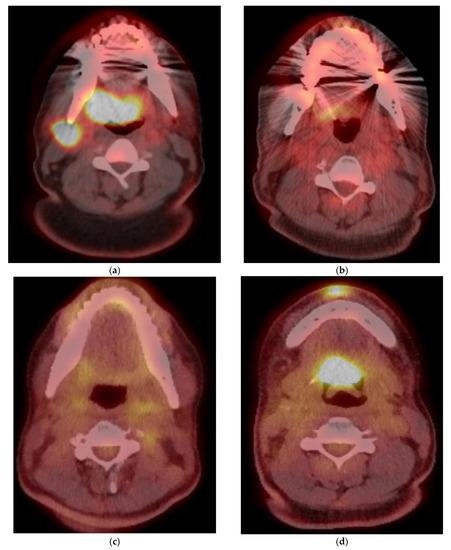

5. Imaging of Oropharyngeal Cancers

8.1. Initial Staging

8.2. Response Assessment